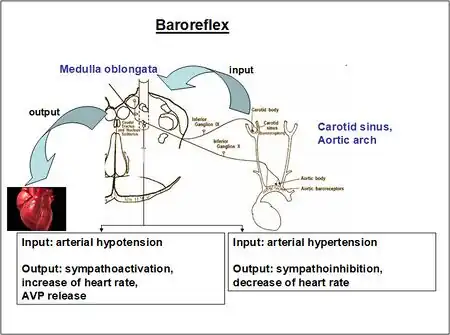

Normally there are homeostatic processes in the body which maintain the concentration of body solutes within a narrow range, both inside and outside cells. The process occurs as follows: in some hypothalamic cells there are osmoreceptors which respond to hyperosmolality in body fluids by signalling the posterior pituitary gland to secrete ADH.[9] This keeps serum sodium concentration - a proxy for solute concentration - at normal levels, prevents hypernatremia and turns off the osmoreceptors.[10] Specifically, when the serum sodium rises above 142 mEq/L, ADH secretion is maximal (and thirst is stimulated as well); when it is below 135 mEq/L, there is no secretion.[11] ADH activates V2 receptors on the basolateral membrane of principal cells in the renal collecting duct, initiating a cyclic AMP-dependent process that culminates in increased production of water channels (aquaporin 2), and their insertion into the cells’ luminal membranes.[12]

Excessive ADH causes an inappropriate increase in the reabsorption in the kidneys of solute-free water ("free water"): excess water moves from the distal convoluted tubules (DCT)s and collecting tubules of the nephrons - via activation of aquaporins, the site of the ADH receptors - back into the circulation. This has two consequences. First, in the extracellular fluid (ECF) space, there is a dilution of blood solutes, causing hypoosmolality, including a low sodium concentration - hyponatremia. [There is no expansion of the ECF volume because as it attempts to expand, aldosterone is suppressed and atrial natriuretic peptide (ANP) is stimulated: both of these hormones cause isotonic ECF fluid to be excreted by the kidneys sufficient to keep ECF volume at a normal level.] Also, virtually simultaneously to these ECF events, the intracellular space (ICF) volume expands. This is because the osmolality of the ECF is (transiently) less than that of the ICF; and since water is readily permeable to cell membranes, solute-free water moves from the ECF to the ICF compartment by osmosis: all cells swell. Swelling of brain cells - cerebral edema - causes various neurological abnormalities which in acute and/or severe cases can result in convulsions, coma, and death.

The normal function of ADH on the kidneys is to control the amount of water reabsorbed by kidney nephrons. ADH acts in the distal portion of the renal tubule (Distal Convoluted Tubule) as well as on the collecting duct and causes the retention of water, but not solute. Hence, ADH activity effectively dilutes the blood (decreasing the concentrations of solutes such as sodium), causing hyponatremia; this is compounded by the fact that the body responds to water retention by decreasing aldosterone, thus allowing even more sodium wasting. For this reason, a high urinary sodium excretion will be seen.